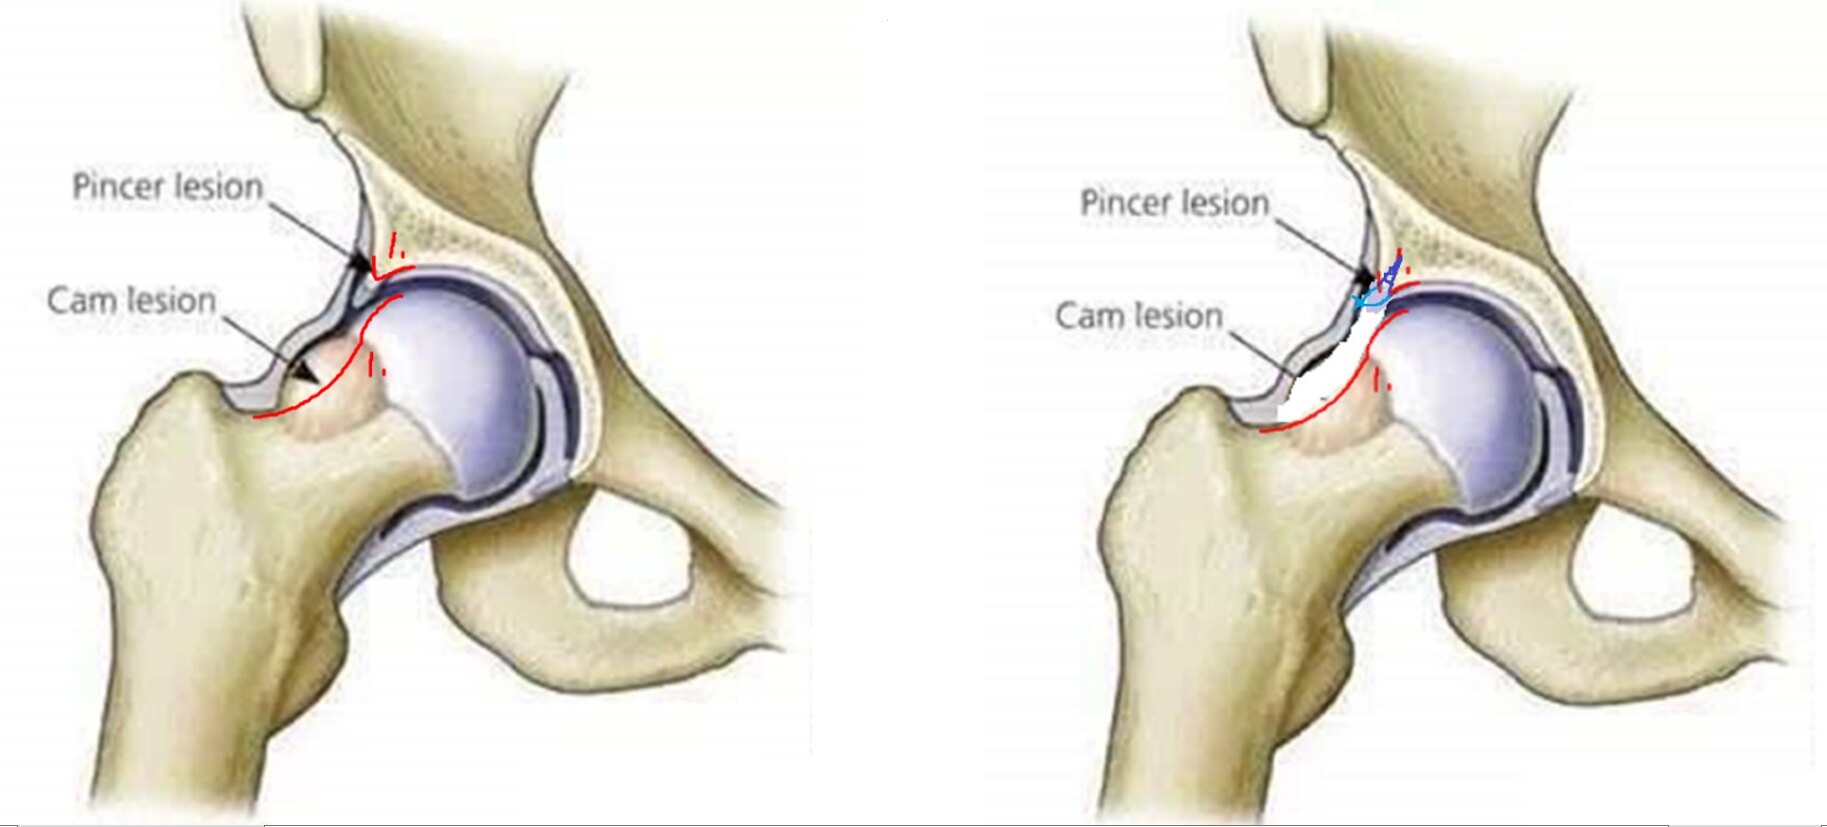

① 凸轮型(cam-type): 股骨头颈交界处异常隆起,屈曲时股骨头颈撞击髋臼缘。

图6.髋关节撞击可由股骨头颈交界处骨质异常隆起造成(凸轮型Cam)。

② 钳夹型(pincer-type): 髋臼前外侧缘太长,屈曲时股骨头颈前侧撞击髋臼缘。

图7.髋关节撞击也可由髋臼前外缘骨质过长造成(钳夹型Pincer)。

③ 混合型(mixed-type):发病率最高,约60%-70%的患者同时出现。

图8.髋关节撞击多数同时存在凸轮(Cam)和钳夹(Pincer)。